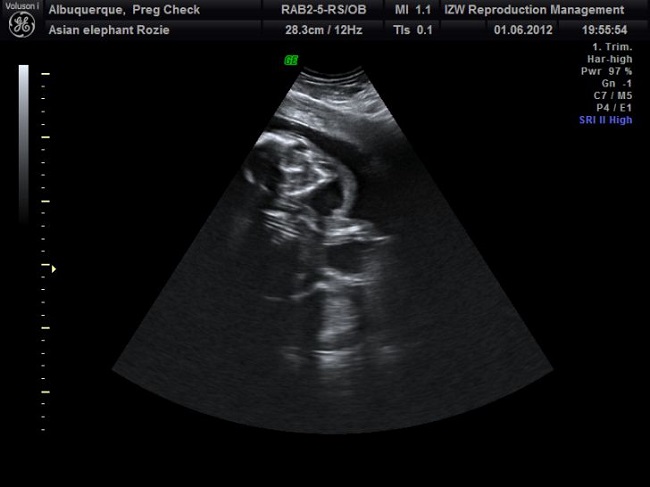

A male elephant’s reproductive tract is about 2 meters long, and in scientific terms, they are called bulls. They start producing sperm from 10 years of age and continue till they turn 15. In the wild, mostly older bulls are more prone to reproduce.

Image Source: diply.com